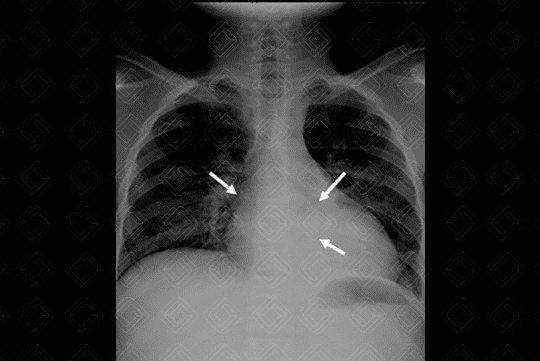

Descrição da lesão: Radiografia de tórax: incidências AP e perfil (figuras 1 e 2, respectivamente). Observa-se na radiografia em AP (figura 1): opacidade arredondada retrocardíaca (setas brancas). Ao analisar a radiografia em perfil (figura 2), deve-se estar atento ao gradiente normal da coluna (os corpos vertebrais superiores devem ser "mais brancos", ou seja, mais radiopacos quando comparados aos inferiores, que naturalmente são mais hipertransparentes). Neste caso, observamos que os corpos vertebrais inferiores estão mais brancos que o habitual, ou seja, o foco de consolidação encontra-se no lobo inferior do pulmão (setas vermelhas). Observação : Sabemos que a consolidação está no pulmão esquerdo, pois observa-se "apagamento" do diafragma esquerdo no perfil, indicando que a pneumonia retrocardíaca visualizada no AP de tórax encontra-se no lobo inferior do pulmão esquerdo.